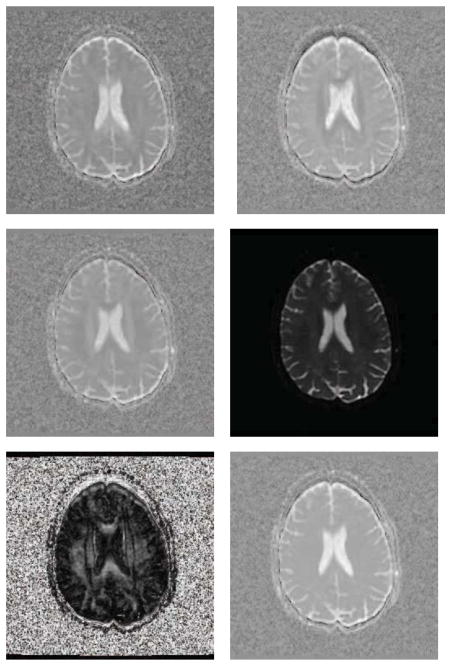

We used a human brain DWI dataset (256 × 256 × 72) provided by Alfred Anwander of the Max Planck Institute for Human Neuroscience (Makuuchi et al., 2009). The DWIs were acquired with a whole-body 3 Tesla Magnetom TRIO operating at 3T (Siemens Medical Solutions) equipped with an 8-channel head array coil. The twice-refocused spin-echo EPI sequence (TR = 12 s, TE = 100 ms) consists of 22 diffusion gradients with a b-value of 800s/mm2.

For the parameters of our model, we chose α = 0.15 and β = 0.45. The search window size is 64 and the neighborhood size is 27. We compared with several other methods on the DTI estimation, however, to save space, we only show the results of MRE, LMMSE and our proposed method. We present D11, D22, D33, S0, FA, and mean trace for each estimated result. The DTI estimation results of MRE, LMMSE and our proposed method are shown in Fig. 6, 7 and 8 respectively. The comparisons indicate that the proposed DTI estimation method generates better results.

Figure 6.

From left to right, top to bottom are D11, D22, D33, S0, FA, and mean trace of the estimated tensor field using MRE on the human brain dataset.

Figure 7.

From left to right, top to bottom are D11, D22, D13, S0, FA, and mean trace of the estimated tensor field using LMMSE on the human brain dataset.

Figure 8.

From left to right, top to bottom are D11, D22, D33, S0, FA, and mean trace of the estimated tensor field using our proposed method on the human brain dataset.